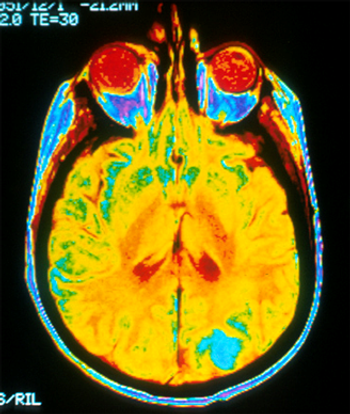

Brain MRIs migraine sufferers reveal abnormalities in cortical thickness and some surface area. These measurements could improve understanding of migraines.

3D MR images reveal some patients show signs of lasting structural damage to the brain after sustaining just one concussion.

Amyloid imaging, used to detect plaques in the brain, may help diagnose cardiac amyloidosis, researchers said.

Brain amyloid PET imaging could assist in diagnosing cognitive impairment in patients who meet certain conditions, according to a new task force.